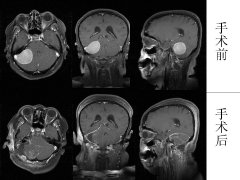

经过充分的术前准备,手术如期进行,由林贵军主任主刀,在手术显微镜下,分离包膜、保护神经、电凝止血,几个小时过去了,肿瘤被一块一块小心地完全切除,所有担心的危险都没有出现,脑干、小脑和神经没有任何损伤。术后病理证实是良性的脑膜瘤。手术后患者恢复很快,未出现任何并发症,几天之后就拆线出院了。

日前,患者来院完成了术后第一次复查,拍核磁片显示肿瘤切除非常干净。她早已回到了原来的工作岗位,恢复了往日灿烂的笑容。